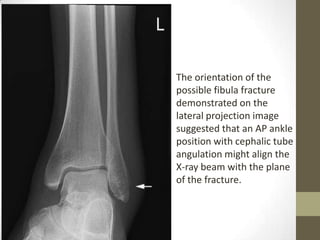

The orientation of the

possible fibula fracture

demonstrated on the

lateral projection image

suggested that an AP ankle

position with cephalic tube

angulation might align the

X-ray beam with the plane

of the fracture.